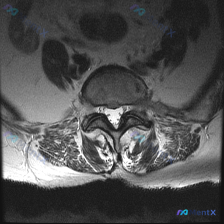

刚整理了一份很有警示意义的读片病例,分享给大家,这个坑平时读片真的很容易踩。 病例基本信息 临床诉求:患者因腰痛就诊,临床怀疑椎间盘病变,提供一张腰椎MRI T2加权轴位影像请读片。 影像基础评估 这是一张腰椎横断面(轴位)T2加权影像,清晰度和信噪比都不错,没有明显运动伪影,可以清楚辨认椎体、椎弓...

看到这张腰椎MRI轴位的椎间盘病例,整理了完整的读片和分析思路,和大家一起讨论。 一、病例影像基本信息 这是腰椎MRI T2序列的轴位影像,层面位于下腰椎水平,可清晰显示椎体、椎间盘、椎管及周围软组织结构: 1. 核心异常信号:椎间盘髓核信号明显减低,呈中等偏低信号,不符合正常髓核的高信号表现,提示...

刚整理完一份腰椎MRI轴位片的读片分析,针对椎间盘病变的问题把完整思路梳理出来,和大家一起讨论。 病例影像基础信息 这是一份腰椎MRI T2序列轴位图像,临床问题是评估椎间盘病变,以下是影像可见的核心表现: 1. 椎间盘:该节段髓核T2信号明显减低,呈均匀低信号,也就是我们常说的「黑间盘」,提示椎间...

看到这一份腰椎MRI读片病例,临床怀疑存在椎间盘病变,我们整理一下影像资料和完整分析思路,大家一起讨论。 病例影像资料 本次提供的是腰椎MRI T2序列轴位图像,分析如下: 1. 扫描层面:位于下腰椎节段,可清晰辨认中央的硬膜囊、马尾神经根,以及侧方的关节突关节、椎旁肌肉 2. 核心影像发现: -...